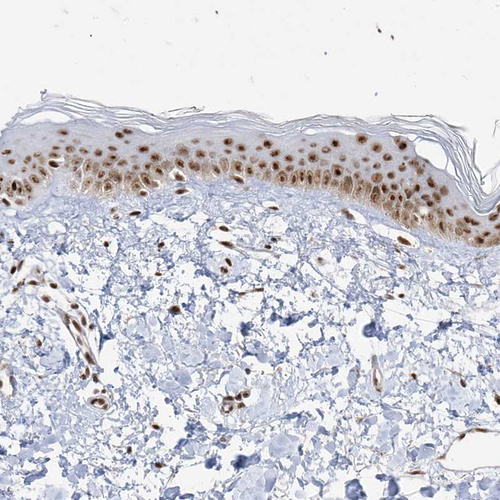

Immunohistochemical staining of human testis shows moderate nuclear positivity in cells in seminiferous ducts.